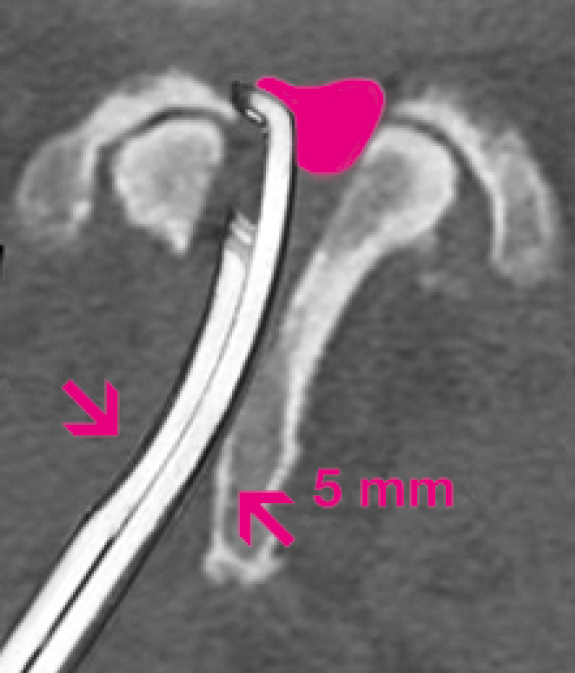

• Ultrathin-foot plate in 2 and 3 mm width